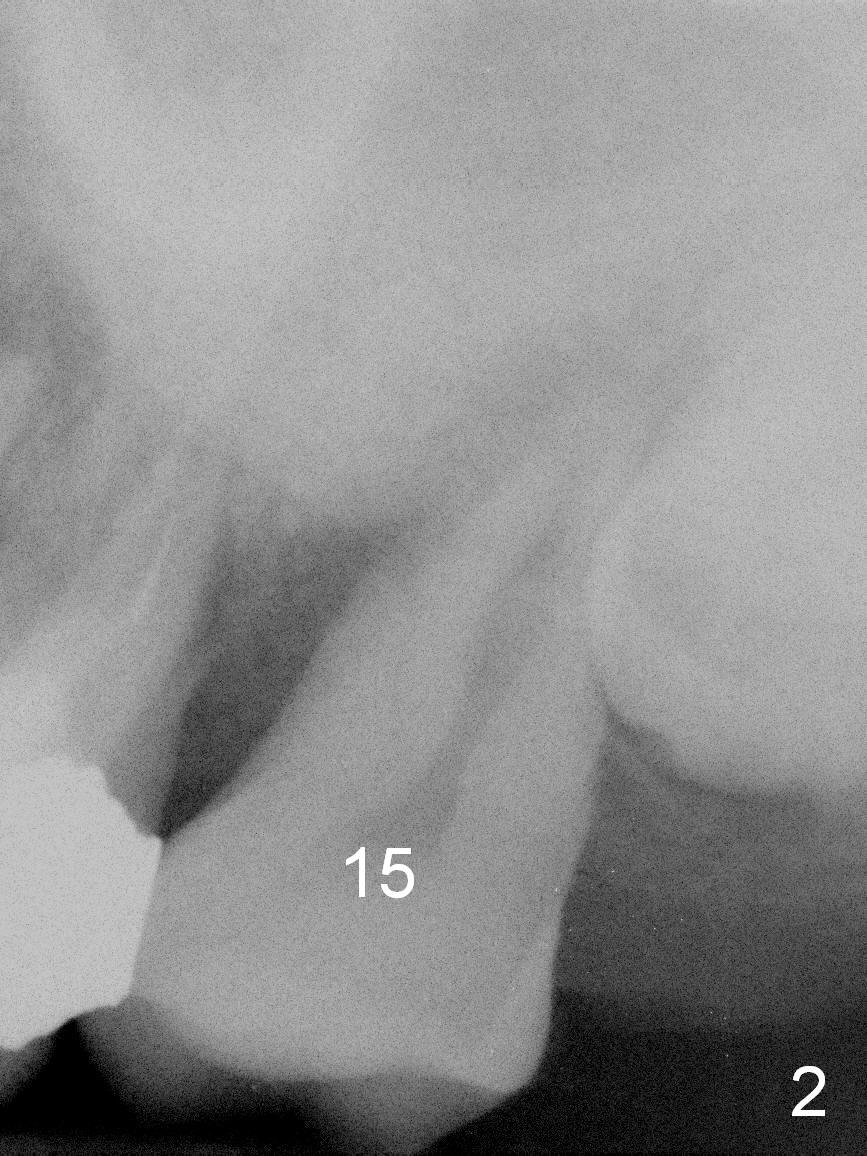

A 51-year-old lady (ZC) requests #15 extraction and immediate implant (Fig.1,2). The affected tooth is between periapical radiolucency of #14 (Fig.1 >) and the impacted 3rd molar (*). Discuss the possibility of extracting #14 and 16 at the same time. After extraction (Fig.3), osteotomy is initiated on the mesial slope of the socket (treated with Clindamycin, Fig.4). Once the cortex is penetrated, the trajectory is changed (Fig.5). After withdrawing the pilot drill, insert a parallel pin for X-ray. Adjust osteotomy position and angulation and finish placing an implant (Fig.6).